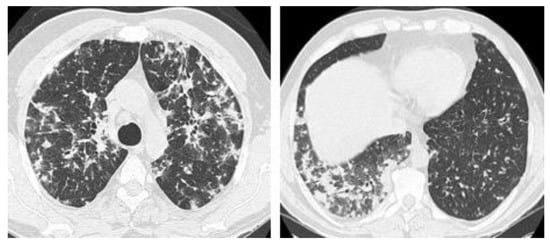

2.2. Non-Resolving Pneumonia

2.5. Mixed Pattern